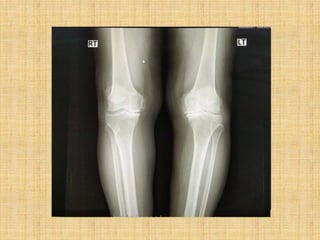

• Lt knee varus deformity swelling, tender, positive crepitus

• Rt. Knee swelling and tender, negative crepitus